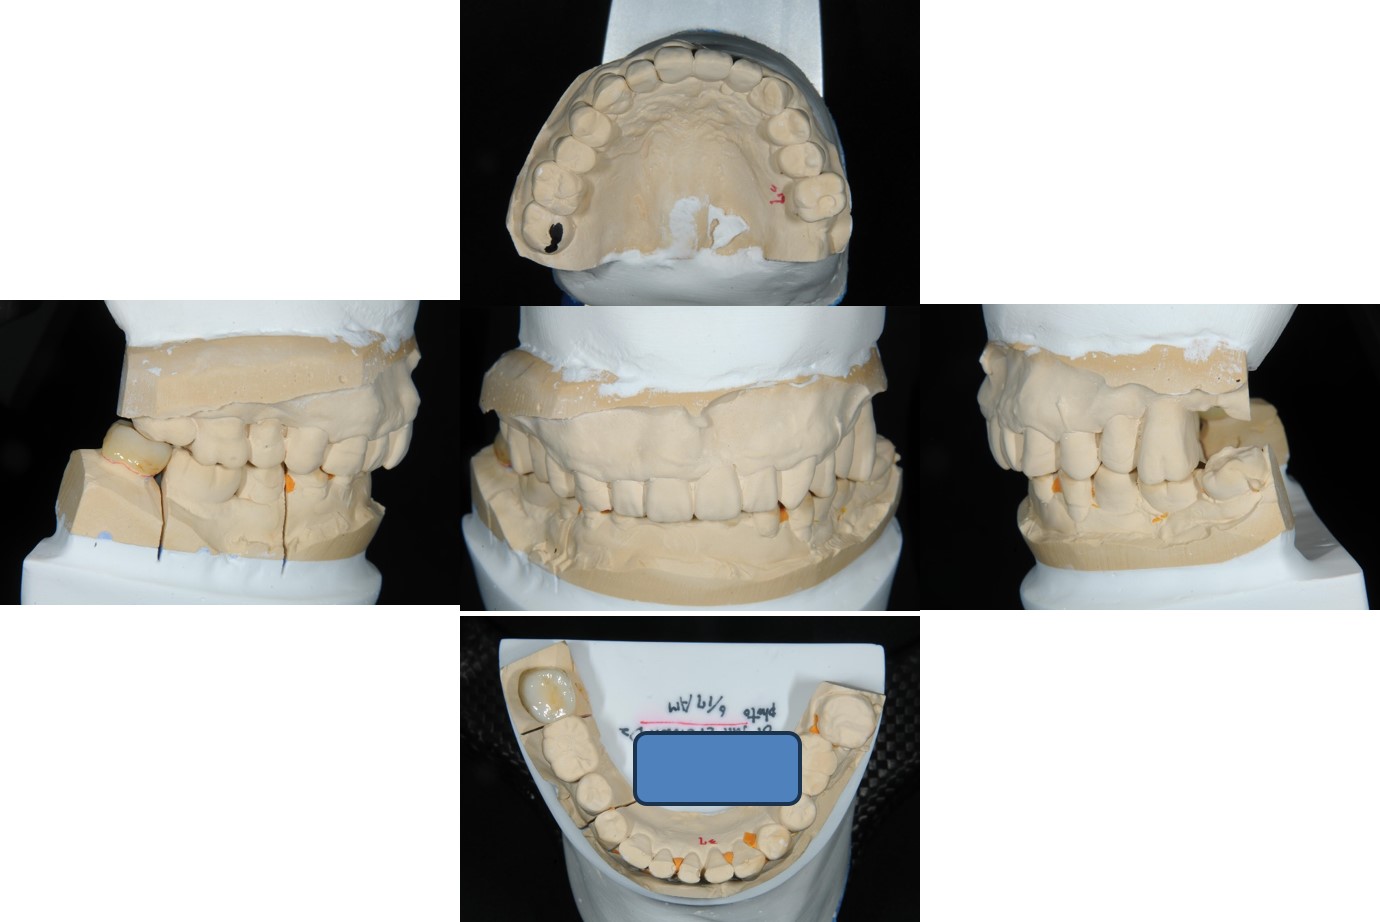

上面弓、上咬合器

技師於咬合器製作全瓷冠

全鋯冠